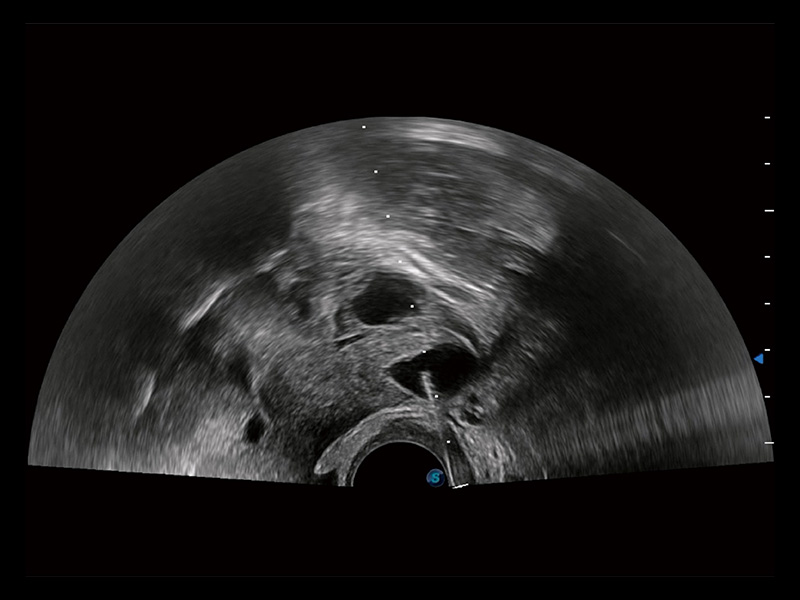

宫外孕血流